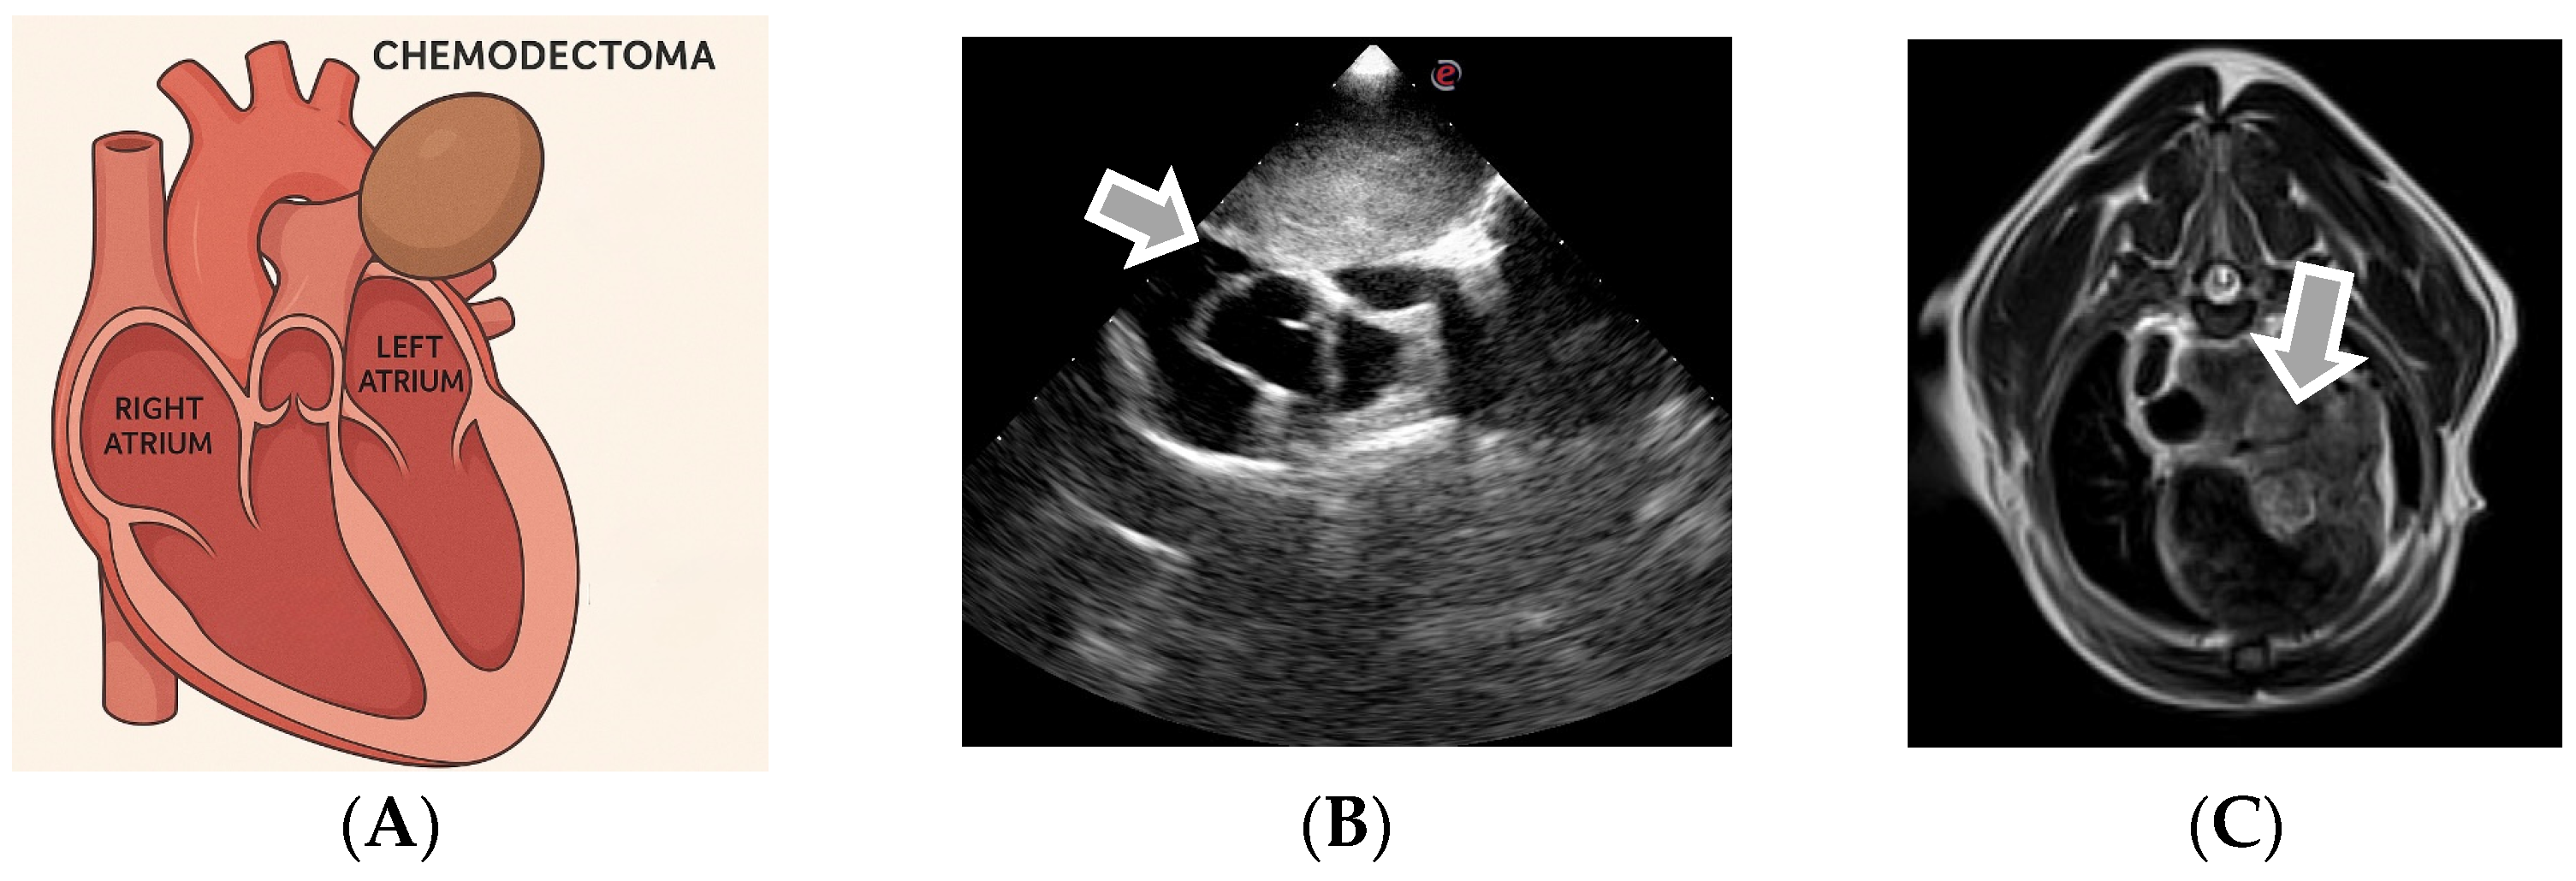

3.3. Echocardiographic Diagnosis of Chemodectoma

| Chemodectoma (Paraganglioma) | Heart base (aortic bifurcation) | Chronic cough, dyspnea, bradycardia, exercise intolerance, tracheal compression |

| Feature | Chemodectoma | Ectopic Thyroid Tumor |

|---|---|---|

| Common Location | The base of the heart, near aortic root and pulmonary artery | Cranial mediastinum, near the base of the heart |

| Vascular Involvement | Encircles pulmonary arteries and may compress atria | Surrounds great vessels (cranial vena cava, aorta) |

| Echogenicity | Homogeneous, hyperechoic | Homogeneous, hyperechoic |

| Mobility on Echo | Non-mobile | Non-mobile |

| Contour | Smooth margins | Smooth margins |

| Growth Speed | Very slow | Slow |

| Infiltration | Extremely rare | None |

| Number of Masses | Typically single | Single |

| Other Clues | Often incidental and predisposed to brachycephalic breeds | May be functional (thyroid hormones) |